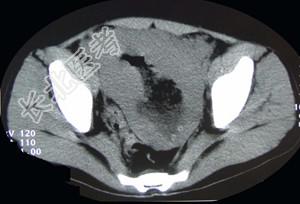

- 单项选择题男,22岁, 下腹部包块,1个月, 伴低热乏力,浅表淋巴结肿大, 影像检查如图,最可能诊断为 ( )

C、肠淋巴瘤